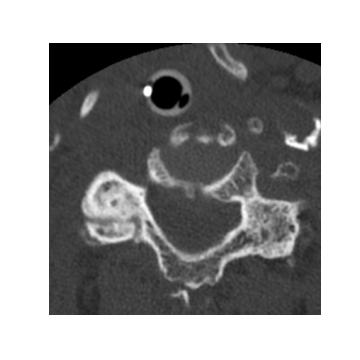

Refer to caption

\alphalph Axial image with three fractures.

\alphalph Heatmap of (a).

\alphalph Axial image with two fractures.

\alphalph Heatmap of (c).

Fig. 3: (a),(c): Samples of cervical spine axial images with fracture; (b),(d): Grad-CAM [10] heatmap from the last layer of ResNet-50 corresponding to (a) and (c), respectively. Ground-truth is represented with red boxes.

Figure 3 shows two samples of axial cervical spine images with corresponding ground-truth masks and heatmaps generated using Grad-CAM [10] from the last layers of ResNet-50. The heatmaps show ResNet-50 can capture most fracture areas with a relatively high false positive rate. Classification performance of the ResNet-50 at image level fracture detection in cervical spine axial images is presented in Table 2. In this experiment, cervical spine fracture is predicted just based on the spatial features in each axial image without counting temporal information. The results show 80.01%percent80.0180.01\% and 77.61%percent77.6177.61\% classification accuracy for the imbalanced and balanced datasets, respectively. However, the main drawback of this approach is the high level of false positives which leads to an inaccurate prediction for the entire case. Such that even if a single image in a case is false positive, the entire case will be false positive and vice-versa. These results show the importance of incorporating temporal features in training and inference. Table 3 shows performance results of the combined BLSTM and ResNet-50 model at the case level for different number of LSTM units. The results regarding the imbalanced dataset show as the number of units increases from 969696 to 256256256, the classification accuracy also increases from 75.79%percent75.7975.79\% to 79.18%percent79.1879.18\%. However, the accuracy is approximately 71%percent7171\% for the balanced dataset and it is less dependent on the number of LSTM units.